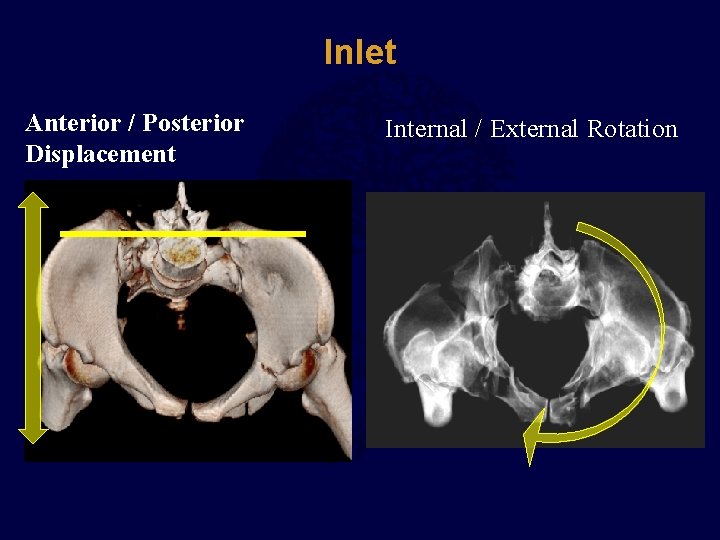

Inlet Anterior / Posterior Displacement Internal / External Rotation